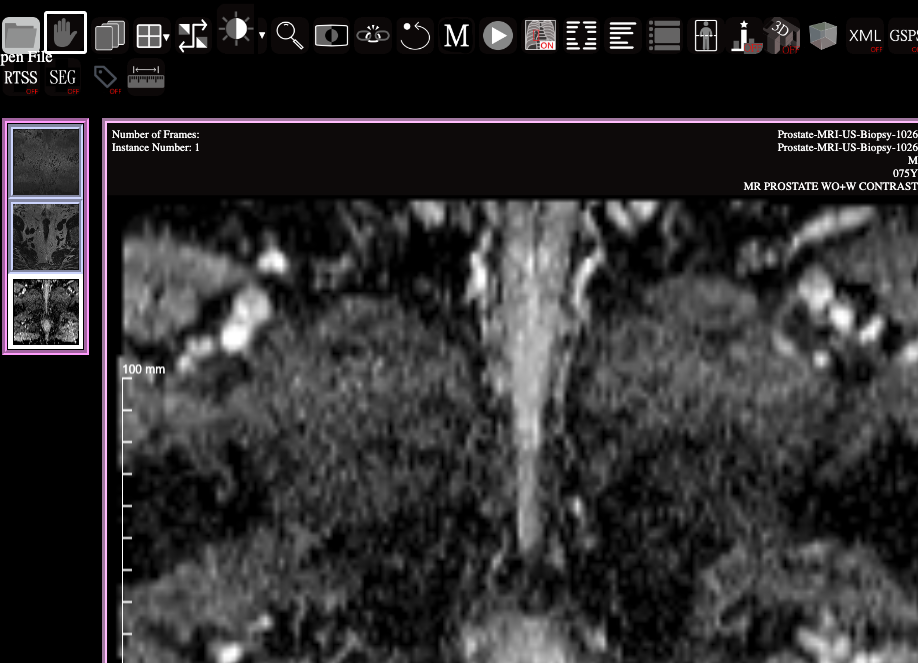

Blue Light is a browser-based medical image viewer is primarily maintained by the Imaging Informatics Labs. It is a pure single-page application (SPA), lightweight, and using only JavaScript and HTML5 technologies so as to deploy it on any HTTP server easily (just put it in HTTP server).

It supports not only opening local data, but also connecting to medical image archives which support DICOMweb. It can display the various image markups and annotations such as Annotation and Image Markup (AIM), DICOM-RT structure set (RTSS), DICOM Overlay, and DICOM Presentation State.

It provides tools for medical image interpretation and 3D image reconstruction, e.g., Multiplanar Reformation or Reconstruction (MPR) and Volume Rendering (VR).